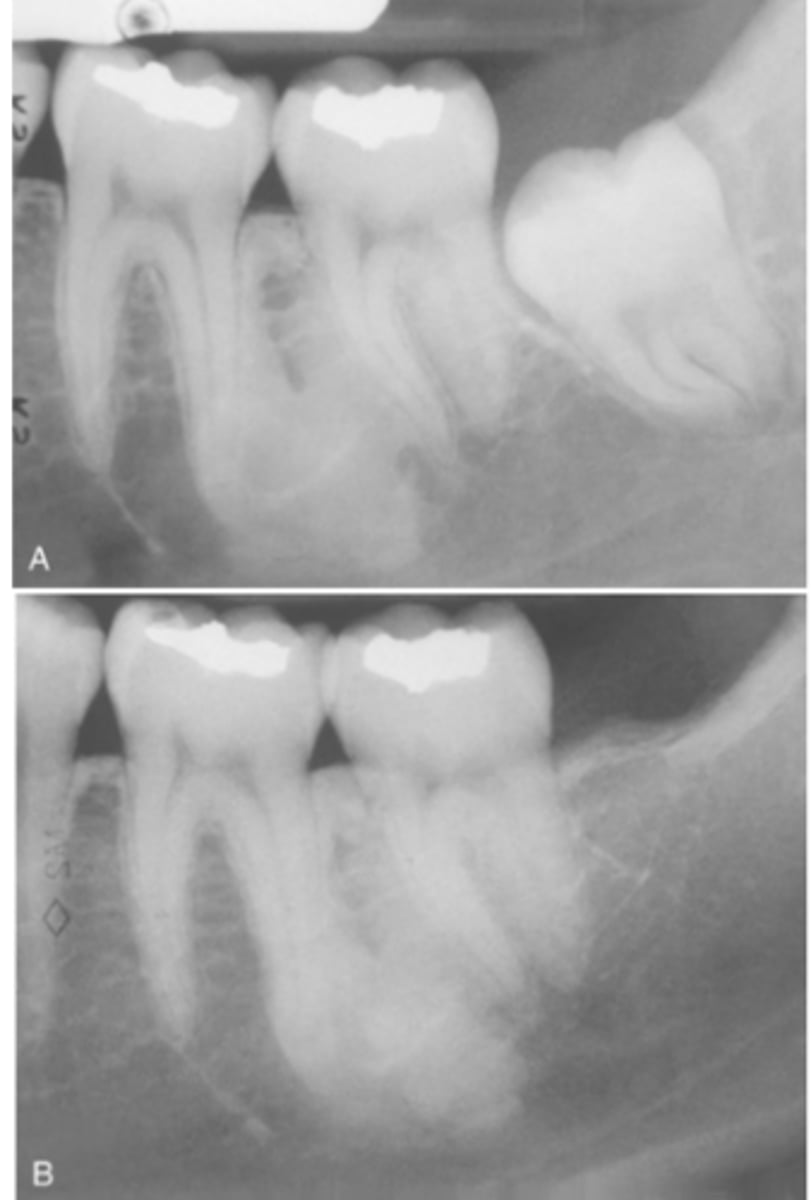

Where are most cases of Idiopathic Osteosclerosis found?

90% of cases affect the mandible

What teeth (in order) in the mandible are most affected in Idiopathic Osteosclerosis

1. First molar area

2. Second molar area

3. Third molar area

What do radiographic signs show in Idiopathic Osteosclerosis

Well-defined radiopacity

Most are associated to a root apex